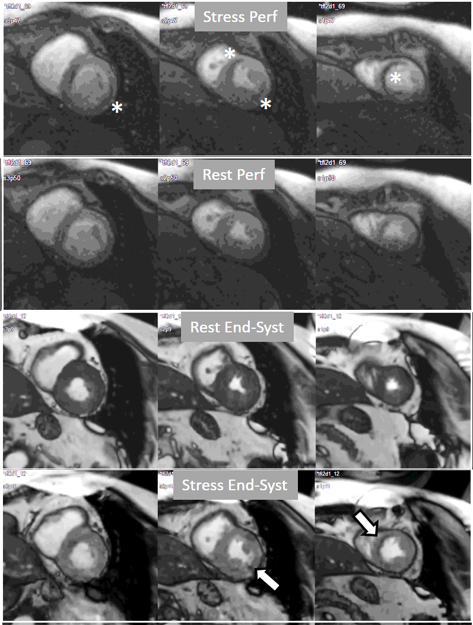

A not infrequent finding is a diffuse, annular, transient, subendocardial defect not present at rest (Fig. 9), which, in the absence of any recognizable obstructive lesion in an epicardial coronary artery, has been deemed to correspond to diffuse microvascular dysfunction (MVD) [41, 42]. CMR perfusion is sensitive to both the downstream effects of discrete epicardial stenoses and those due to disturbances of coronary microcirculation, and subendocardial hypoperfusion is on the pathophysiological basis of each one. For this reason, theoretically, a global, inducible subendocardial defect, could also be due to multivessel epicardial disease with balanced ischemia. In practice, however, this latter instance presents with extensive but heterogenous defects in terms of intensity, persistence and transmurality and, not rarely, also with perfusion defects at rest (Fig. 10A). Importantly, an accompanying induced contractile disfunction may be found in particularly impaired regions (Fig. 10B), a finding which is never seen in MVD.

Fig. 10.Multi-vessel perfusion defect. (A) Global stress hypoperfusion in a patient with multivessel CAD. Observe the non-uniformity of the defect, with different degrees of intensity and transmurality and, also, with the presence of a defect at rest (arrow), in the absence of LGE. (B) End-systolic frames from cine studies at the same level of the perfusion slices showing inducible antero-septal hypokinesia during stress (arrows).